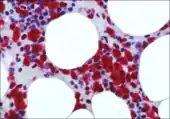

Falini's research contributions fall in the area of precision medicine. His scientific activity ranges from the field of monoclonal antibodies for diagnostic and therapeutic purposes to genomic studies on AML and hairy cell leukemia (HCL). His discoveries of NPM1 mutations in AML and BRAF-V600E in HCL, identified new mechanisms of leukemogenesis and resulted into improvement of the diagnosis, prognostic stratification, molecular monitoring and therapy of these hematological malignancies.[2]

In 2005, stemming from his immunohistological studies on ALK-positive ALCL, Falini discovered that tumor cells from about one-third of adult AML (mostly carrying a normal cytogenetic) expressed aberrantly in the cytoplasm nucleophosmin (a nucleolar located protein). This finding prompted Falini and colleagues to sequence the NPM1 gene and to discover heterozygous mutations at exon 12, responsible for the aberrant nuclear export of the NPM1 mutant protein.

Falini's group also demonstrated that NPM1 mutations are AML specific and associated with a de novo origin of the disease.[9] His research team then identified molecular variants of NPM1 mutations (other than exon 12), clarified the molecular mechanisms underlying the ectopic cytoplasmic accumulation of the NPM1 mutants[10] and proposed that it plays a critical role in leukemogenesis. Falini and colleagues also discovered a unique gene expression and microRNA profile of NPM1-mutated AML and demonstrated that over-expression of HOX genes is closely related to the cytoplasmic delocalization of NPM1 mutants.[11]

Falini's team also demonstrated for the first time that NPM1 and FLT3-ITD mutations frequently co-occur in AML patients and proposed their cooperative role in promoting leukemia.[9] Assessment of the NPM1 gene status and monitoring of measurable residual disease (MRD) by RT-quantitative PCR of NPM1 mutant copies (first reported by the Falini's group)[12] is now recommended by the LeukemiaNet for genetic stratification and guiding therapeutic decisions in AML patients.[13]